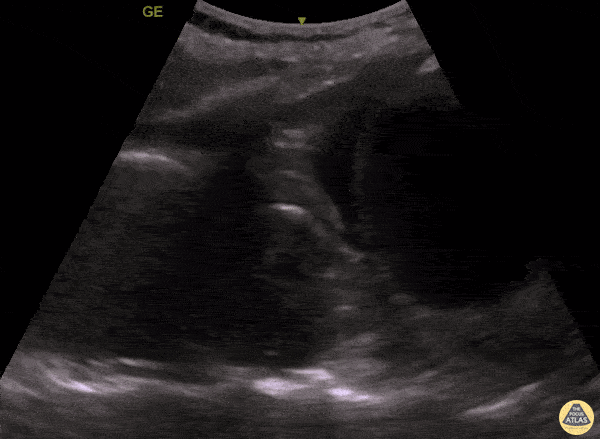

Aorta - Thoracic Aortic Aneurysm Rupture Seen on PLAPS View

An elderly woman presented to the ED with dyspnea and left mid back pain for 1 week. Left PLAPS (Posterolateral Alveolar and/or Pleural Syndrome) view revealed a round-shaped pulsatile mass surrounded by pleural effusion & atelectatic lung. CTA later confirmed a partially ruptured, thrombosed thoracic aorta aneurysm. This case illustrates the possibility of quickly diagnosing life-threatening conditions with POCUS. Contributed by: Caio Sangirardi, Emergency Medicine Resident Quinta D'Or Hospital, Rio de Janeiro - Brazil, @SangirardiMD